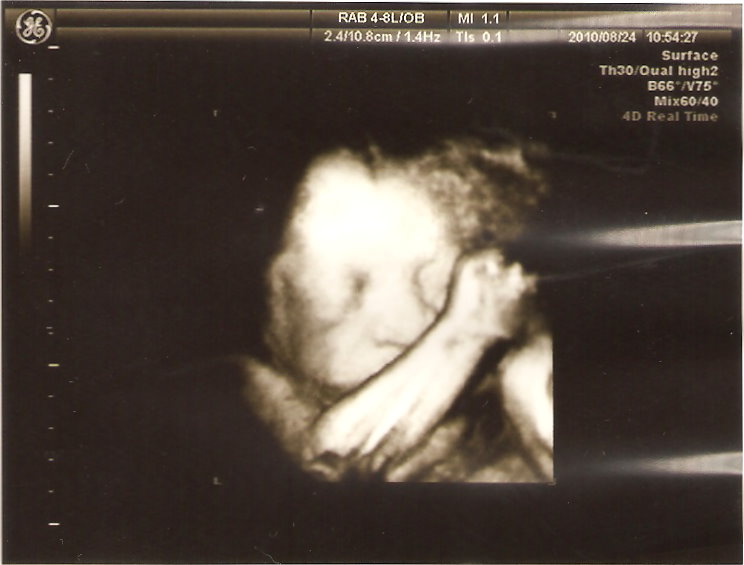

本來都看不太到臉,頭低低又用手遮住臉的臭小子,竟在這個時候被醫生拍到他在微笑

是的,微笑!我跟我姊都很明顯的看到他在笑,真想呼一巴掌給他

不過平常滾得天翻地覆的他檢查時竟然裝乖都不太動,醫生常常用超音波推肚子,還叫他快起來

果然人少時不一樣,上次人太多,看不到就算了,醫生根本沒空等他動啊~